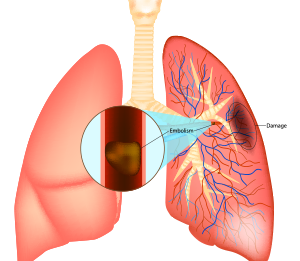

Sex Differences in Pulmonary Embolism

June 14, 2021

Take the Quiz

Evaluate Pulmonary Embolism

January 12, 2021